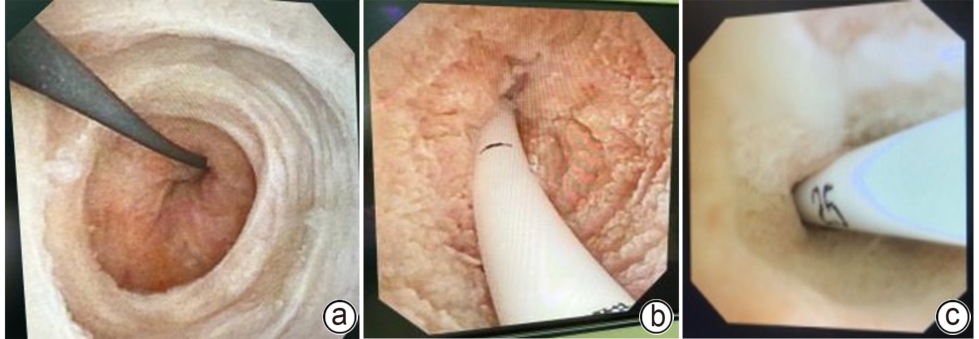

Therapeutic effect of different biliary drainage methods after laparoscopic common bile duct exploration in elderly patients with choledocholithiasis: An analysis based on propensity score matching

Kaifang DU, Xichun WANG, Lei WEI, Changzhi ZHAO, Zhongyi FENG, Mingjie CHENG, Hanshuo LI, Guiling LANG

2025, 41(11): 2359-2364. DOI: 10.12449/JCH251124

Abstract(324) HTML (139) PDF (6943KB)(65)

Abstract:

Objective  To investigate the safety and feasibility of intra-biliary drainage tube placement after laparoscopic common bile duct exploration in elderly patients with choledocholithiasis, and to provide more options for surgical procedures in the clinical management of elderly patients with choledocholithiasis.  Methods  A retrospective analysis was performed for the clinical data of 52 elderly patients with choledocholithiasis who were admitted to Department of Hepatobiliary Surgery, Affiliated Dalian Friendship Hospital of Dalian Medical University, from November 2021 to October 2024. According to the biliary drainage method after surgery, the patients were divided into internal drainage group with 24 patients and T-tube drainage group with 28 patients, and there were 19 patients in each group after propensity score matching. The two groups were compared in terms of perioperative parameters and postoperative complications. The Wilcoxon rank-sum test was used for comparison of continuous data between two groups, and the chi-square test or the Fisher’s exact test was used for comparison of categorical data between two groups.  Results  Compared with the T-tube drainage group, the internal drainage group had a significantly shorter length of postoperative hospital stay and a significantly lower volume of postoperative bile loss (Z=-2.845 and -5.633, both P<0.05), while there were no significant differences between the two groups in time of operation, intraoperative blood loss, and drainage tube indwelling time (all P>0.05). There were no significant differences between the two groups in postoperative bile leak, stone recurrence, biliary stricture, and drainage tube-related complications, and the internal drainage group had a significantly lower total complication rate than the T-tube drainage group [1 (5.3%) vs 7 (36.8%), P<0.05].  Conclusion  For elderly patients with choledocholithiasis, intra-biliary drainage tube placement after laparoscopic common bile duct exploration can shorten the length of postoperative hospital stay, reduce bile loss, and lower the incidence rate of postoperative complications, thereby helping to accelerate postoperative recovery.